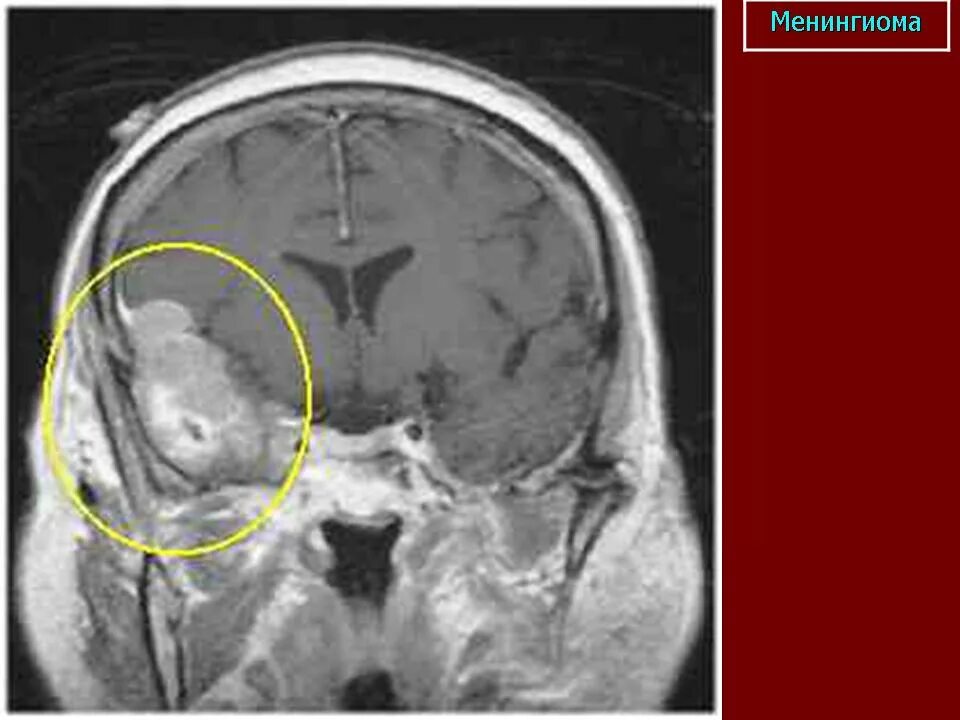

Менингиомы головного мозга мкб